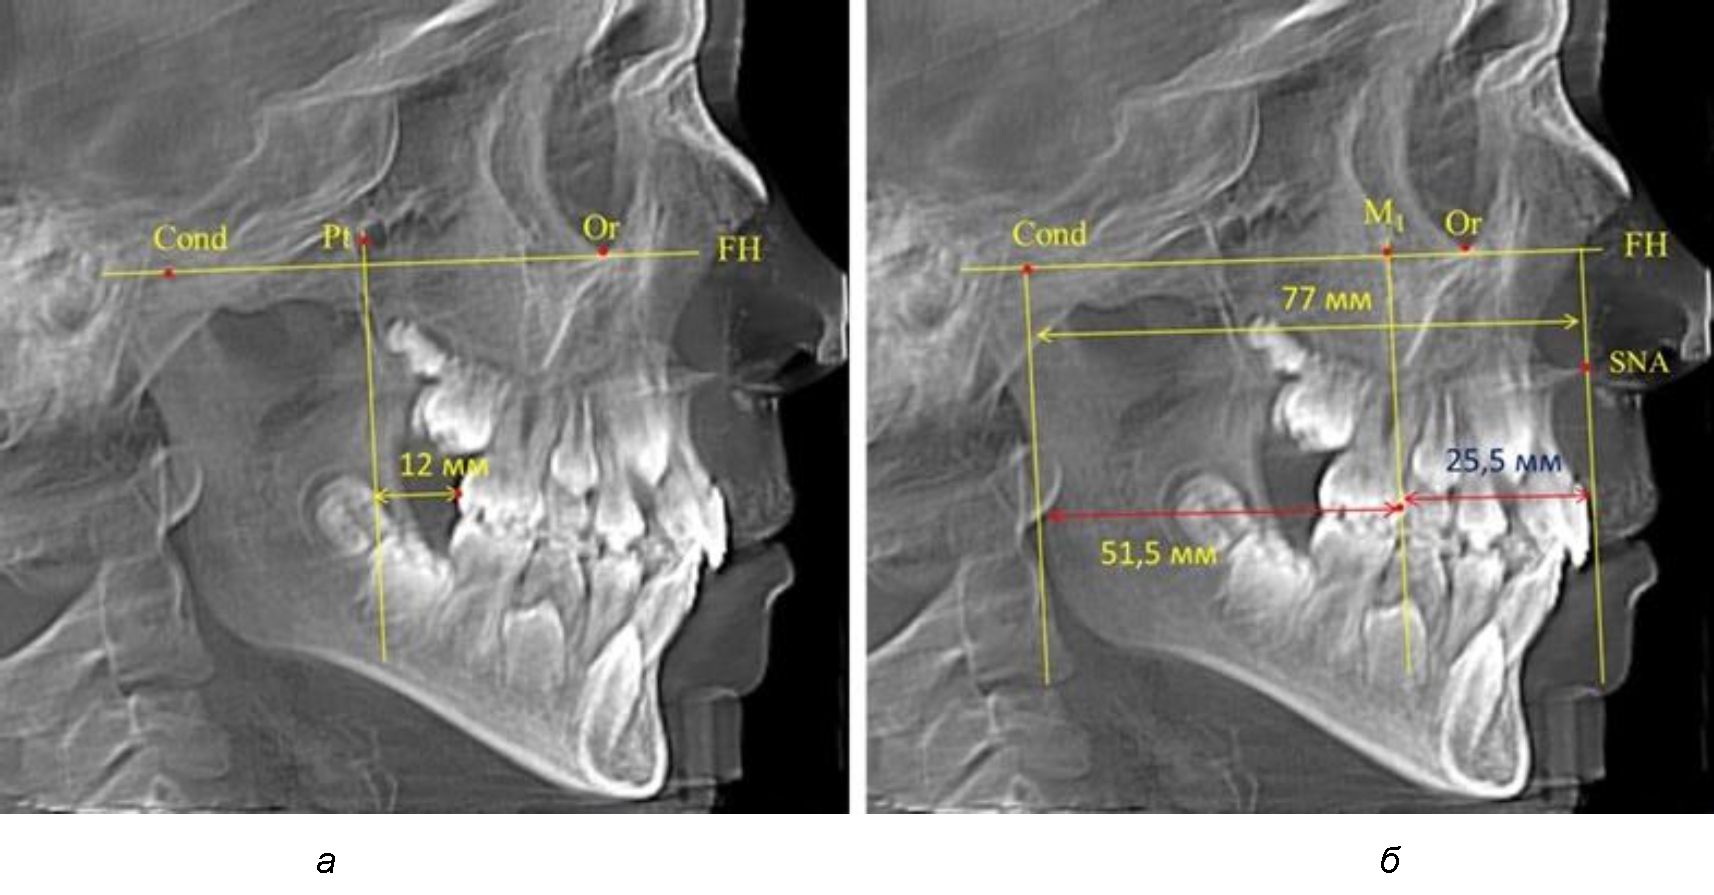

Так, при расстоянии от крыловидной вертикальной плоскости PTV до дистальной поверхности верхнего первого постоянного моляра в 13 мм сагиттальный размер гнатического отдела был 82 мм. При этом отношение кондилярно-спинального расстояния к кондилярно-молярному размеру (54,5) было близким к коэффициенту 1,5, что представлено на рис. 2.

Рис. 2. Особенности положения первых моляров по R. E. McDonald (а) и по предложенному методу (б) при уменьшенном молярно-крыловидном расстоянии